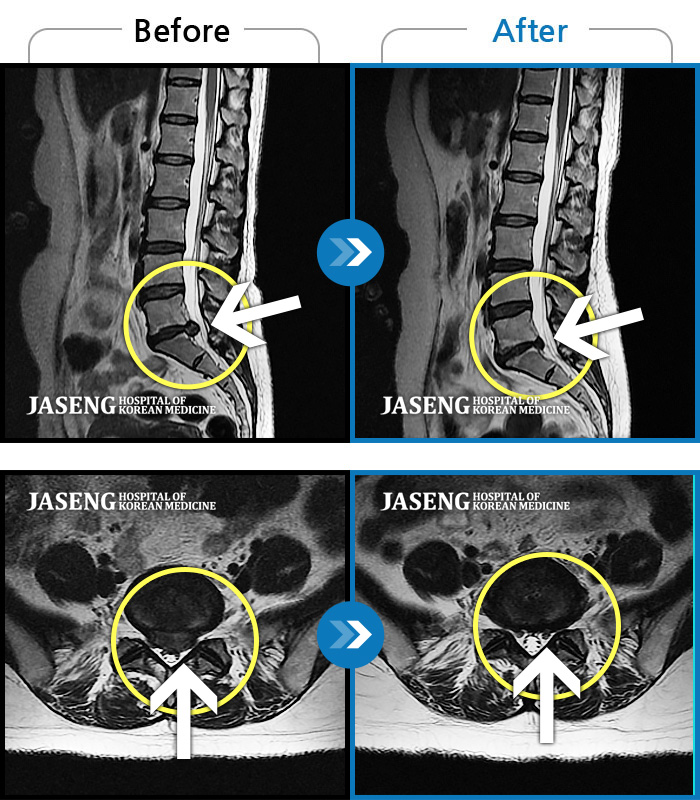

[뱸] 19.11.28~25.05.06